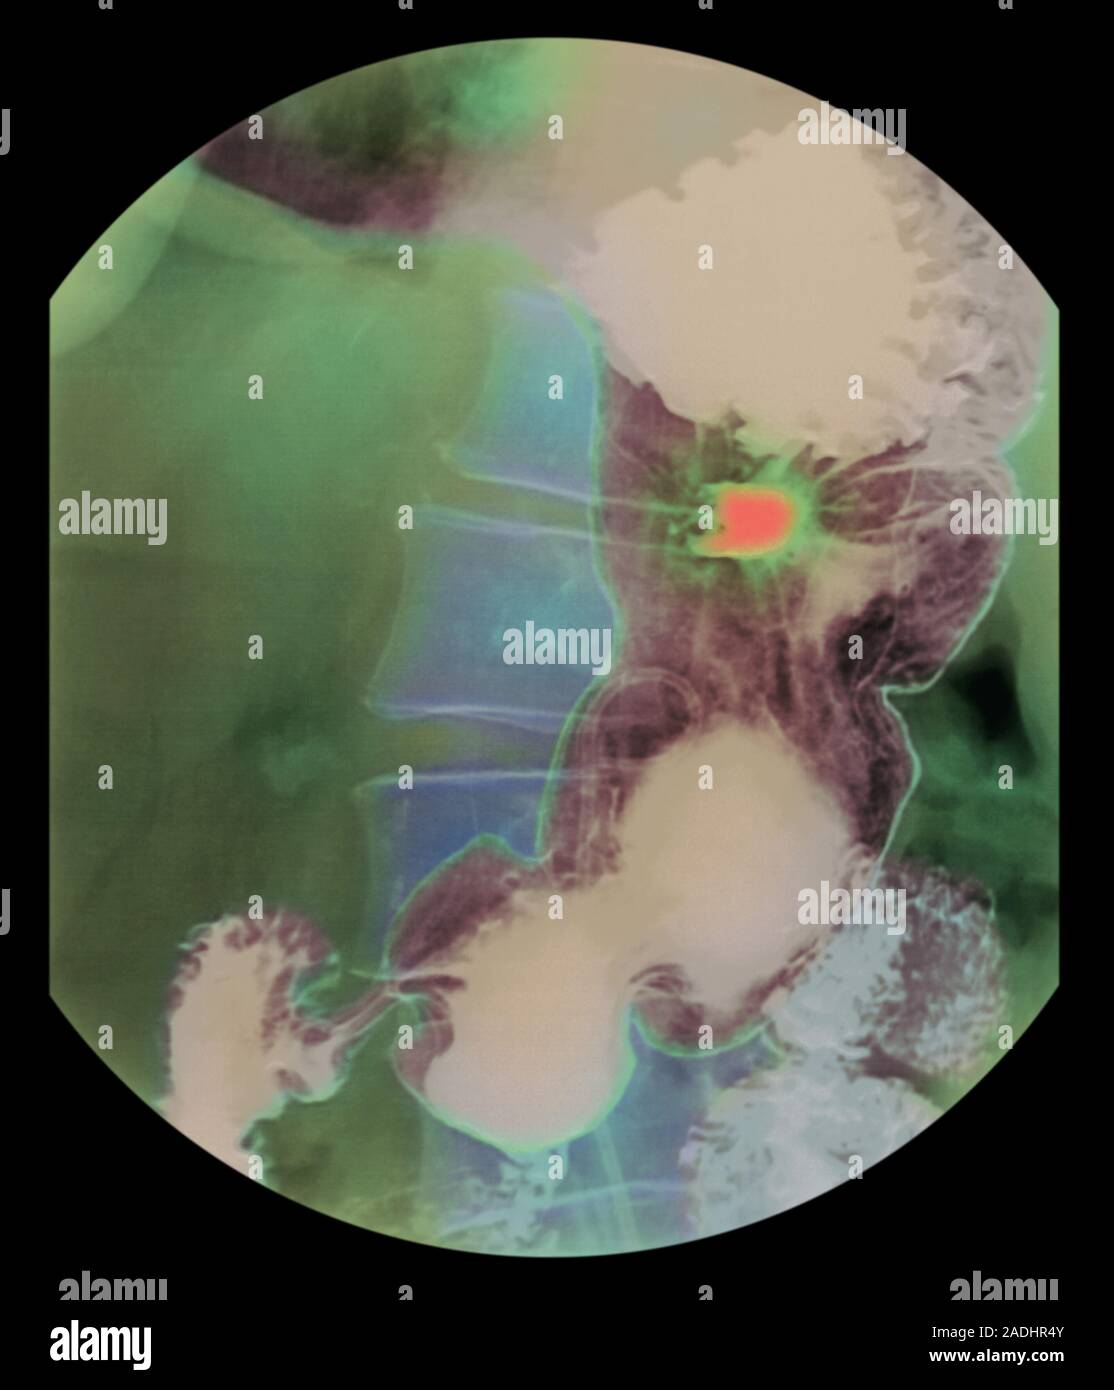

Stomach ulcer. Coloured barium Xray of a patient's stomach (brown) showing the position of a Tea Pot Deformity  There are descriptions of the deformity called ‘tea pot’ stomach in literature, but there are no reported cases. Stenotic complications of peptic ulcer disease are hour glass deformity and tea pot deformity (gastric ulcer). The deformity occurs due to. There are descriptions of the deformity called ‘tea pot’ stomach in literature, but there are no reported cases. Gastric outlet obstruction. Tea Pot Deformity.